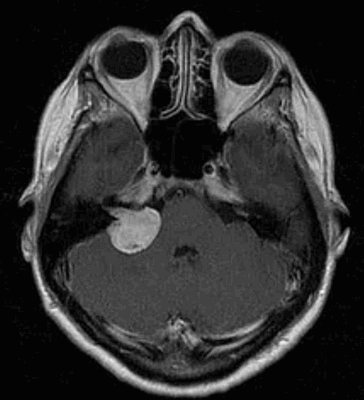

В результате выполненной 02.12.15 МРТ головного мозга с контрастным усилением, показавшей наличие интраканальной опухоли, распространяющейся в сторону мостомозжечковой цистерны, заподозрена невринома слухового нерва. Было принято решение проводить динамическое наблюдение. Однако 14.12.15 остро развилась слабость лицевой мускулатуры, стала нарастать интенсивность головокружений. Внепланово была выполнена контрольная МРТ головного мозга 13.01.16, где отмечалось увеличение экстраканальной части опухоли почти в 2 раза. В течение подготовки к хирургическому лечению отмечалось значительное ухудшение состояния: нарастание статодинамических нарушений, увеличение выраженности симптоматики со стороны правого мостомозжечкового угла, появление бульбарных нарушений, выраженных общемозговых симптомов. По МРТ головного мозга от 22.02.16 отмечалась прогрессия экстраканальной части опухоли до 3 см. На фоне терапии глюкокортикоидами, обезболивающими и противорвотными препаратами состояние пациентки стабилизировалось.